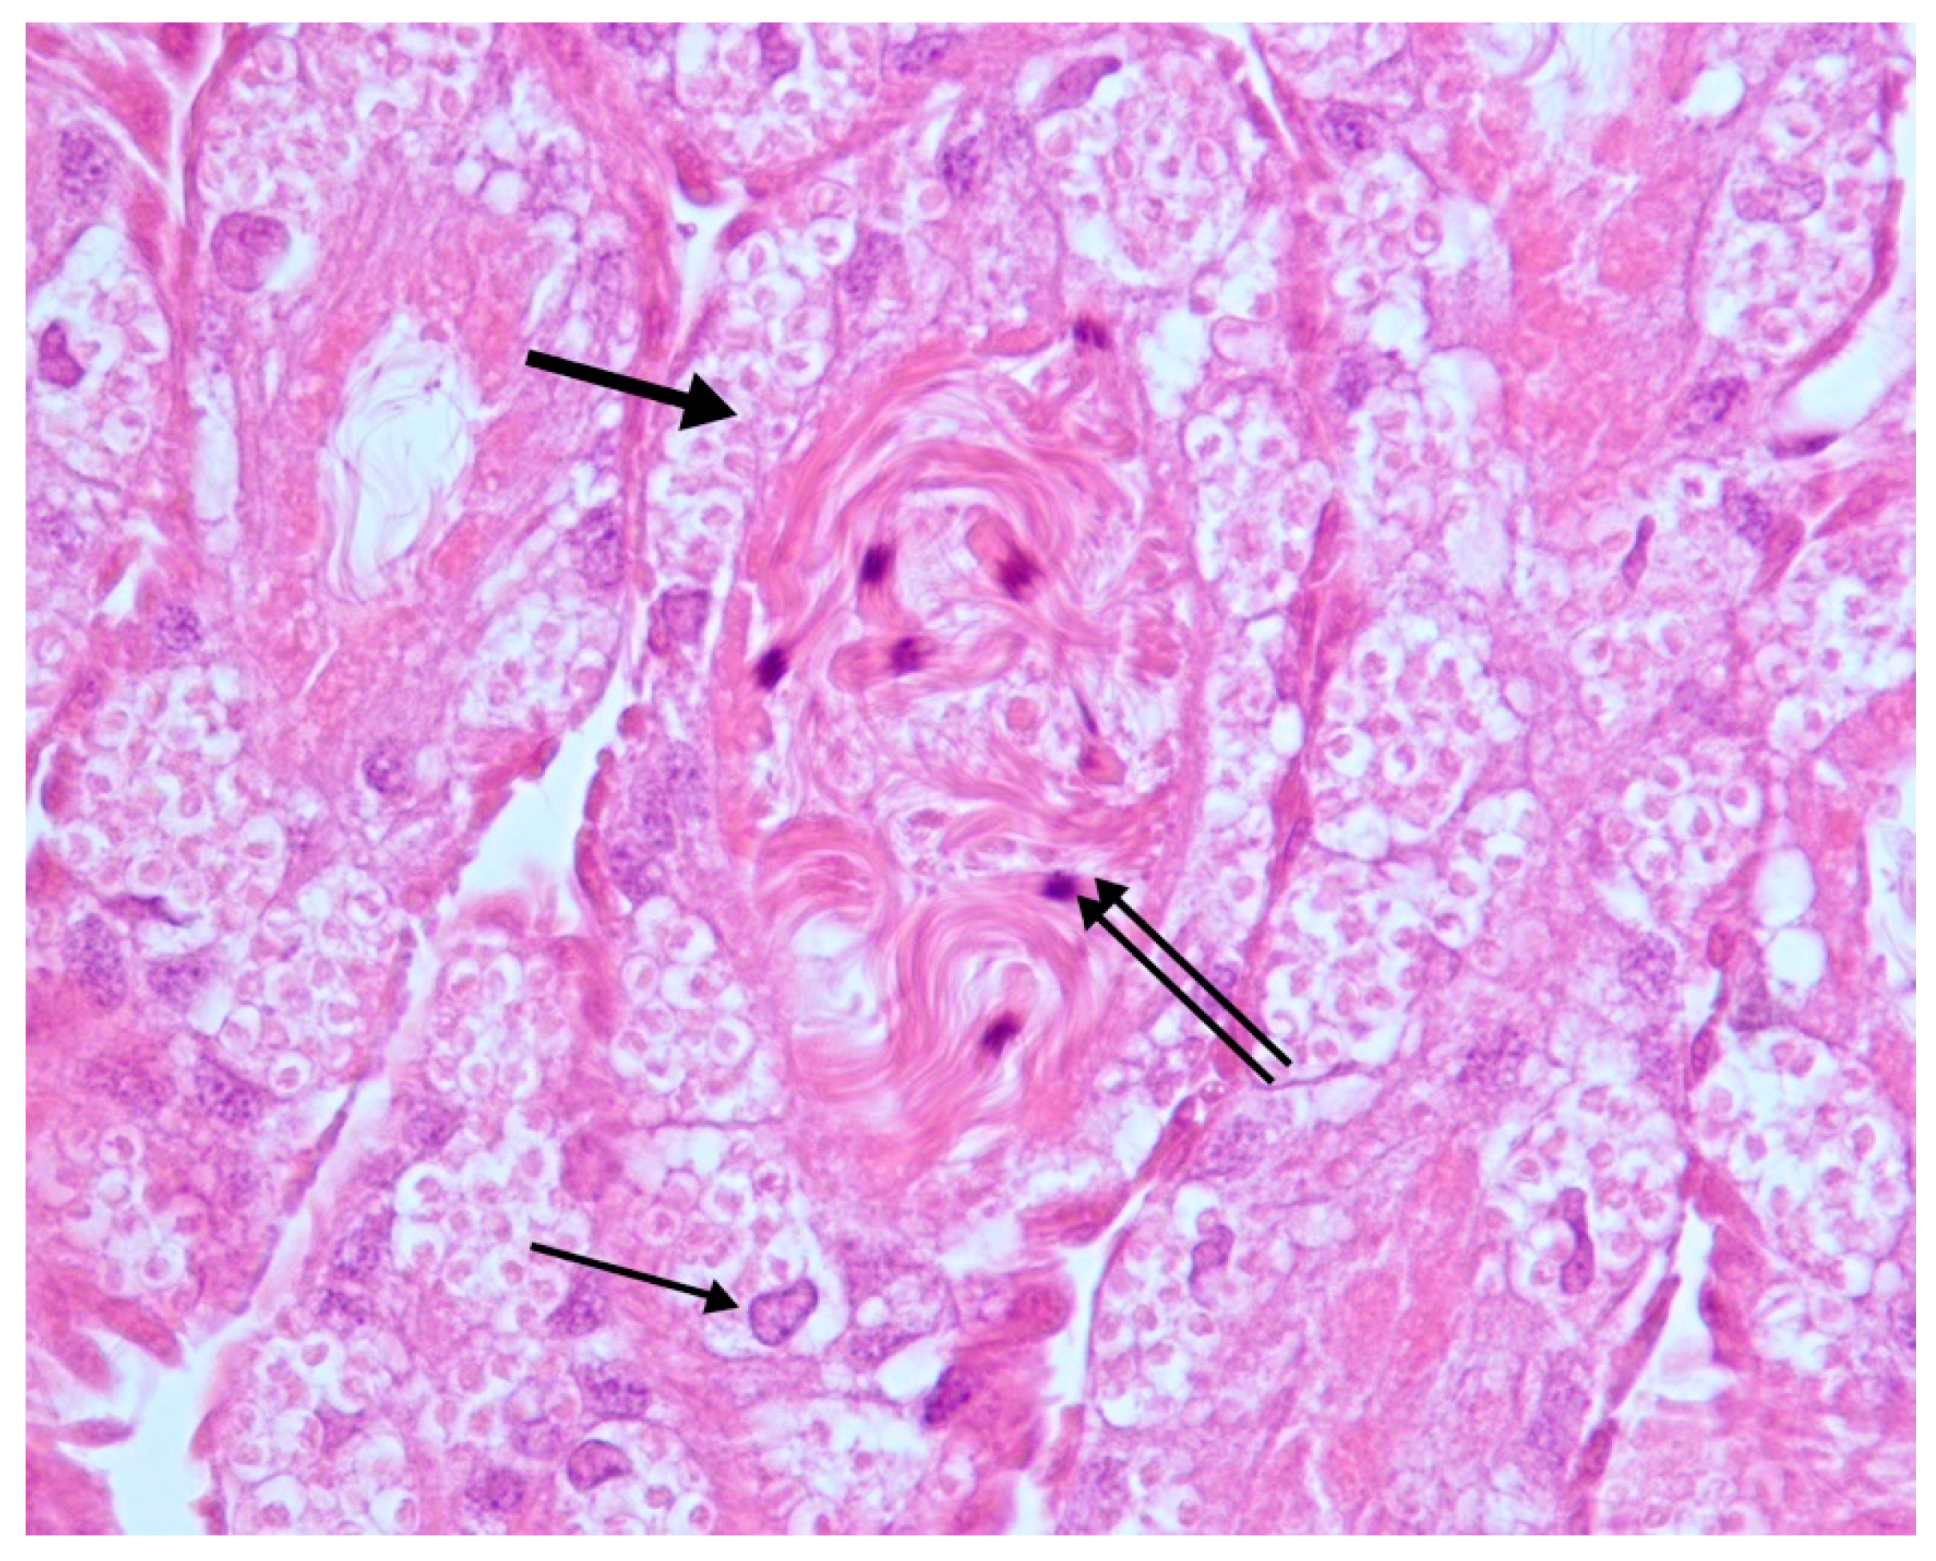

Macroscopically, samples showed no visible alterations and were aged 10 to 27 days old. Samples processed with the protocol described above appeared well preserved since tissues were well stained, and no artifacts were seen. Microscopically, 17/25 samples showed healthy testes that appeared as elongated, bean-shaped structures with numerous seminiferous tubules, surrounded by an external epithelial layer (seminiferous epithelium). The seminiferous tubules contained follicular and germ cells that encapsulate to form a thin wall cyst; the tubular lumen was filled with many coiled spermatozoa (Figure 1).

Figure 1.

Testes. Normal seminiferous tubules. Follicular (thin arrow) and germ cells (thick arrow); coiled spermatozoa in the lumen of the tubules (double arrow). H-E 40×.